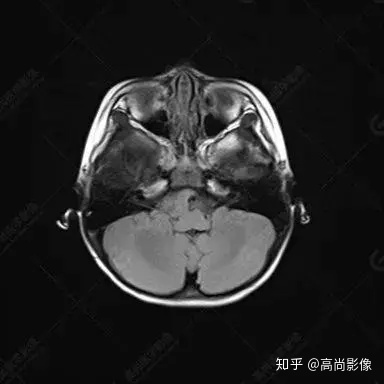

右側(cè)顳葉腫瘤切除術(shù)后(具體不詳):右側(cè)顳部骨質(zhì)不連續(xù)呈術(shù)后改變,右側(cè)顳葉術(shù)區(qū)見片狀長T1長T2信號(hào)影,F(xiàn)LAIR呈低信號(hào);術(shù)區(qū)后方右側(cè)顳枕葉見一巨大占位性病變影,邊界欠清,大小約6.2×5.8×4.3cm(前后×左右×上下),信號(hào)不均勻,T1WI呈等稍低信號(hào)間雜少許高信號(hào),T2WI呈高稍低混雜信號(hào),DWI示部分病灶彌散受限,相應(yīng)ADC圖減低,磁敏感序列見部分呈極低信號(hào),增強(qiáng)掃描可見明顯不均勻強(qiáng)化,鄰近硬腦膜及小腦幕增厚并明顯強(qiáng)化;另延髓右前方及右側(cè)橋小腦角區(qū)見一不規(guī)則形異常信號(hào)影,大小約3.2×1.3×3.7cm(左右×前后×上下),呈長T1稍長T2信號(hào),F(xiàn)LAIR呈等信號(hào),DWI未見受限,增強(qiáng)后明顯均勻強(qiáng)化,鄰近腦膜明顯強(qiáng)化。鄰近腦實(shí)質(zhì)及右側(cè)顳角明顯受壓;左側(cè)大腦半球未見局灶性信號(hào)異常,中線結(jié)構(gòu)稍左移。

右側(cè)顳葉腫瘤切除術(shù)后:現(xiàn)術(shù)區(qū)后方右側(cè)顳枕葉及延髓右前方占位,右側(cè)顳枕部硬腦膜及小腦幕明顯強(qiáng)化,結(jié)合既往影像資料,考慮為胚胎源性惡性腫瘤,如非典型畸胎樣/橫紋肌樣瘤(AT/RT)或原始神經(jīng)外胚層腫瘤(PNET)。